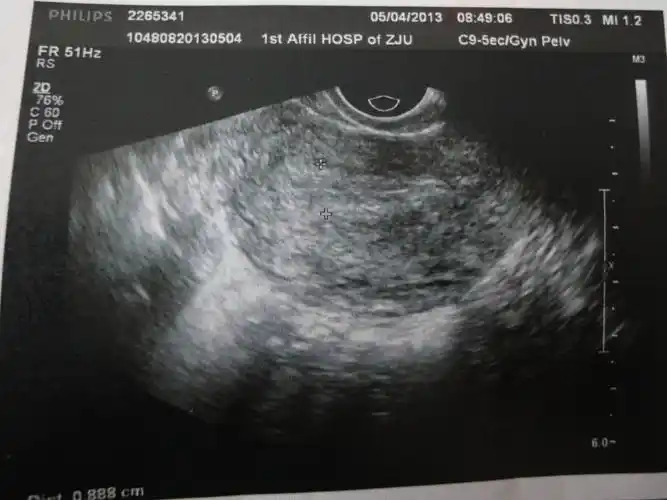

超声微课堂阴道超声检查规范

阴超这样正常吗?

今天去做阴超看卵泡只看楼主

两次阴超,到底是何种病?(最新上传化验结果)

经阴彩超图片请会诊